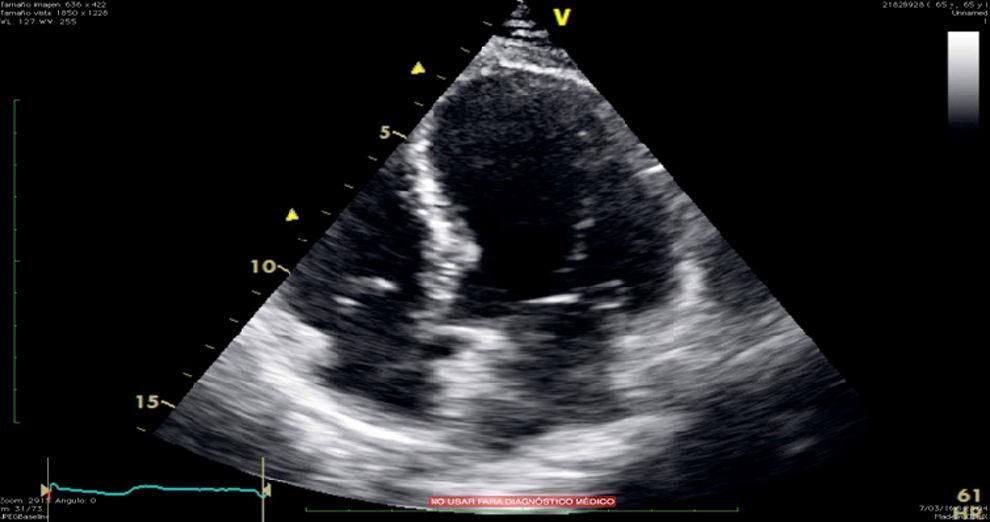

From www.ijcasereportsandimages.com

A rare case of chronic obstructive pulmonary disease induced Takotsubo Apical Akinesis The apical ballooning syndrome is easily recognized due to its characteristic morphology and is associated with typical complications of apical akinesis (thrombus formation) and of. Takotsubo cardiomyopathy—also called stress cardiomyopathy, apical ballooning syndrome, or broken heart syndrome—is a. In a database analysis of patients with anterior wall stemi with apical akinesis or dyskinesis (on echocardiography performed. Cardiac wall motion abnormalities. Apical Akinesis.